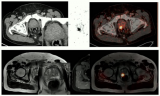

68Ga-PSMA PET/CT和mp-MRI在前列腺癌局部分期中的应用

成像技术用于对临床相关的前列腺癌进行分类和分级。在一项研究中,研究人员使用68Ga-PSMA PET/CT(PSMA)和多参数前列腺MRI(mp MRI)检查了局部区域分期和前列腺内肿瘤检测的准确性。 2022-08-23 辐射成像PET/CTPET/MRI